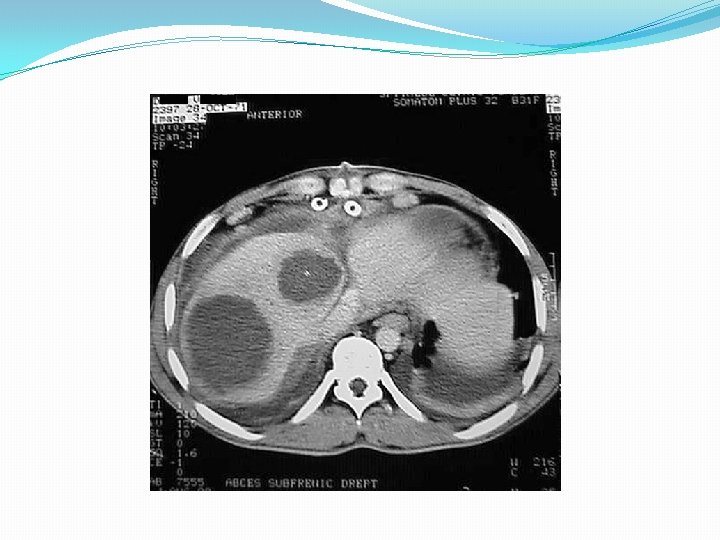

Imagistica �TC abdominala are o sensibilitate (de 97%) mai mare decat ecografia, deceleaza microabcesele (0, 5 cm) precum aduce informaţie şi despre patologia abdominală asociată – precizînd focarul de plecare.

Imagistica �Radiografia simplă (funcţionarea cupolei diafragmale, reacţia sinusului pleural, imagini hidroaergice, pneumobilia).